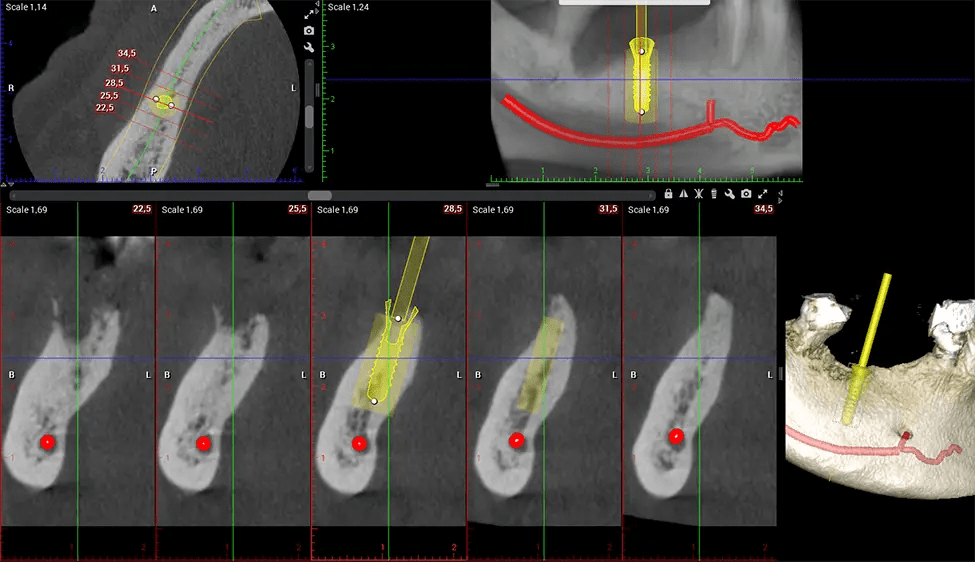

Cone Beam Computed Tomography (CBCT) is an advanced imaging technique used in dentistry and maxillofacial surgery to obtain detailed 3D images of the oral and maxillofacial structures. At Dr G Dental Studio, our CBCT scanners utilize a cone-shaped X-ray beam and a specialized detector to capture images from different angles. A computer then combines these images to create a 3D representation of the patient’s oral anatomy.

This 3D scan, called cone beam computed tomography, gives your dentist a more complete image of your oral anatomy and disease processes than a traditional X-ray. Unlike conventional X-rays, which capture a 2D image of your mouth from various angles, a 3D scan takes multiple digital X-rays for one image. It provides a complete view of your jaw, teeth, nerves, and soft tissues. This enhanced view allows dentists to detect minor issues not visible in traditional 2D scans, such as impacted wisdom teeth or bone fractures in the sinus cavity.

After the scanning process, the captured X-ray images are processed by the CBCT software, which applies algorithms to reconstruct a detailed 3D image of the scanned area. The software compiles these individual X-ray images and creates a digital 3D representation of the patient’s anatomy. The reconstructed 3D CBCT image can be viewed and analyzed by the dentist or radiologist. This image can be manipulated, rotated, and zoomed in or out to examine specific structures and evaluate the patient’s condition.